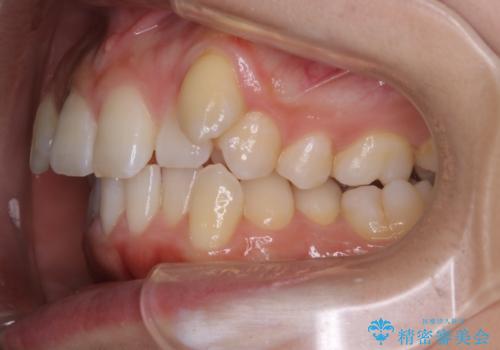

- 上顎の八重歯が気になるとのことで来院されました。

左側のかみ合わせは、歯1本分かみ合わせが前にずれていました。上顎左右の奥歯を2本抜歯しています。

下顎は、歯の側面を少し削ることで歯並びを整えました。

上顎と下顎の奥歯の抜歯(計4本)を行う治療方法もありますが、口元のバランスのことも考え、上顎の抜歯のみで、治療を行いました。

八重歯でがたつきは重度でしたが、きれいな歯並びにすることができました。

がたつきだけでなく、奥歯の噛み合わせのずれの調整もしっかり行いました。

奥歯のずれの調整は時間がかかりますが、矯正後の歯並びの安定度が向上します。